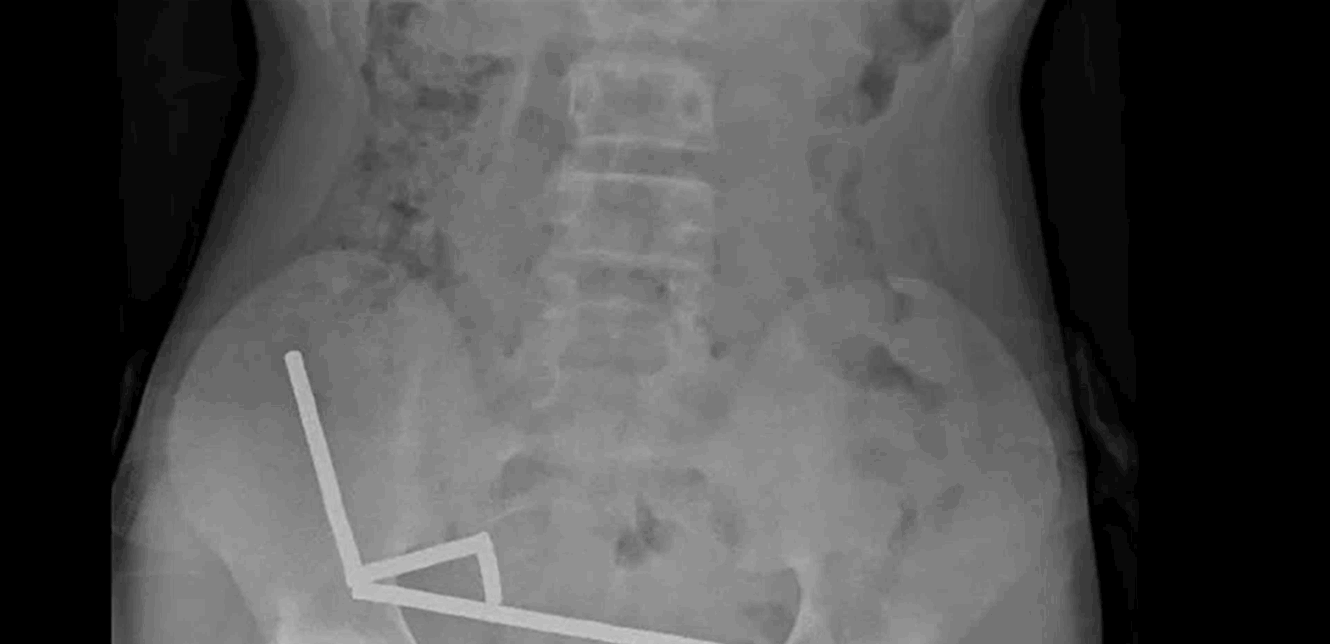

وقال التقرير أن الطفل "أكد أنه ابتلع ما يقرب من 80-100 مغناطيس عالي الطاقة (نيوديميوم) بأبعاد 5x2 مم قبل حوالي أسبوع". وأضافوا أن المغناطيسات، التي حُظرت في نيوزيلندا منذ يناير 2013، تم شراؤها من منصة التسوق الإلكترونية تيمو. وأظهرت الأشعة السينية أن المغناطيسات قد تكتلت معًا في أربعة خطوط مستقيمة داخل أمعاء الطفل.

وشرح التقرير: "يبدو أن هذه المغناطيسات كانت في أجزاء منفصلة من الأمعاء ملتصقة ببعضها البعض بسبب القوى المغناطيسية". كما أفاد الأطباء بأن ضغط المغناطيس تسبب في نخر (موت الأنسجة) في أربع مناطق من الأمعاء الدقيقة والأعور (جزء من الأمعاء الغليظة) للصبي.